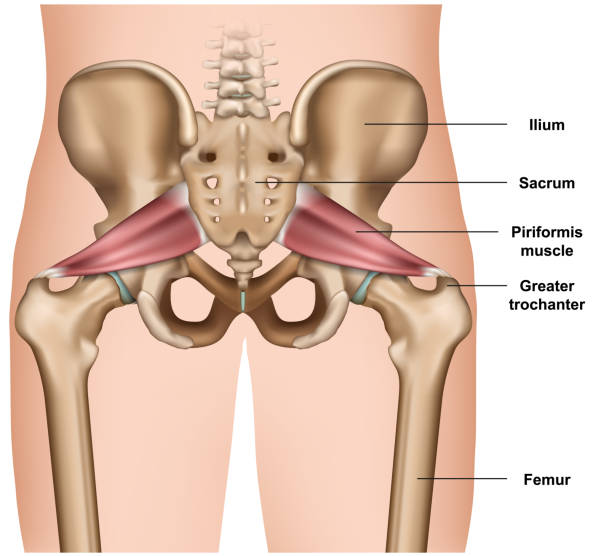

Understanding Cystocele and Rectocele: Causes, Symptoms, and Treatment Options Pelvic floor disorders such as cystocele…